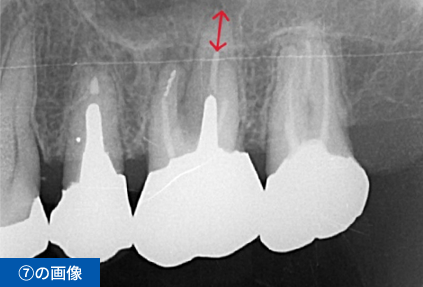

左下④56⑦番のブリッジの脱離にて来院(④⑦はブリッジの支台歯56は欠損)

| 費用 ※保険外診療 | 総額1,485,000円(税込) インプラント3本、手術2回、CGF、遊離歯肉移植、CT撮影、被せ物の型取り(印象)、被せ物(フルジルコニア)3本、投薬 |